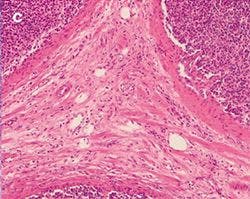

The practical effect of the color shift caused by a generic LED light source, both with and without a CC filter, is clearly visible when imaging a stained tissue section using the different light sources. Figure 5 shows a tissue section illuminated by the three different light sources mentioned before.

Figure 5: Stained Tissue Section c

Differences between halogen lamp (a) and LED illumination (b) lead to tissue stainings shifting to blue, both through the oculars and on the screen. Adding a CC filter (c) mitigates the issue, but still gives a yellowish appearance.